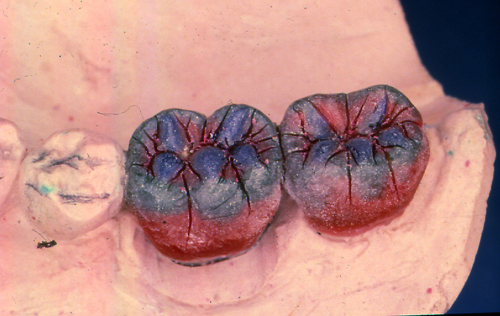

INTRODUCCION La rehabilitación oral como especialidad multidisciplinaria, obliga al profesional a pensar en términos complejos, donde la observación de todos y cada uno de los elementos constituyentes del sistema Estomatognático se hace imprescindible para el arribo a un diagnóstico de certeza. Sabido es que el esmalte dentario se desgasta con el correr de los años. Sin embargo, es importante determinar como se produce dicho desgaste y si éste responde a una cuestión de carácter fisiológico o se trata de una manifestación patológica. Adaptativas Tienen paca velocidad de desgaste. Su localización es exclusivamente de esmalte. No hay deformación oclusal y se producen cuando el sistema neuromuscular es aún inmaduro. Madurativas En la oclusión adulta los contactos interoclusales son puntiformes, ya que contactan convexidades contra convexidades. Parafuncionales Son las únicas que podemos considerar patológicas. Su velocidad de desgaste es mucho mayor y se localizan en dentina, pudiendo o no ser sintomáticas. En los anteriores el desgaste puede ser plano y parejo, lo que significa que el paciente bruxa en sentido anteroposterior. Si por el contrario, el desgaste es curvo, el bruxismo es de carácter latero-lateral. En los posteriores podemos observar en casos avanzados que las cúspides estampadoras presentan una facetamiento mayor que las cúspides de corte, ya que en las lateralidades aquéllos que rozan el doble de veces que éstas últimas, dando lugar al llamado desgaste “en olla” e invirtiendo la curva de Wilson. MATERIAL Y MÉTODOS En el desarrollo de este trabajo se utilizaron onlays de oro (Ventura 120). CASO CLÍNICO El paciente se presenta a la consulta derivado y con severas mialgias difusas y referidas fundamentalmente a la cara, región posterior del cuello y ocasionalmente en la región occipital y temporal. Mujer 55 años, prácticamente sin historia odontológica anterior, ya que dice tener una dentadura excelente y que sólo visita a su dentista con relativa periodicidad para limpiezas, ya que caries cree no tener. Se evidencian signos depresivos cuando manifiesta que no sabe como dar solución a su problema. El examen periodontal denota bolsas poco profundas salvo en el incisivo superior lateral izquierdo, que también ofrece una moderada movilidad y ligeramente vestibulizado. El examen de la ATM determina la presencia de ruidos articulares en apertura y cierre y dolor a la palpación. Durante este examen manifiesta haber tenido dificultades para la apertura en reiteradas ocasiones. Fig 1/2 Se toman modelos de estudio y se duplican. Antes de proceder a su correspondiente montaje en un articulador semiajustable, se observan individualmente cada uno de3 ellos haciéndose ya objetiva la presencia de facetas de desgaste que, sin duda, tienen un origen y que nos darán la clave de nuestro diagnóstico (Fig. 3). Montados ya los modelos en oclusión en relación céntrica, mediante el que considero el más fisiológico medio de obtención de la misma: las laminillas de Long, preconizado por el Dr. W.H. McHorris (*), y que nos permite romper con los engramas o patrones de memoria muscular que trae el paciente y que en muchos casos, como éste, llevan a la mandíbula fuera de su posición esqueletal fisiológica, y que la obliga a trabajar en medio de contracturas musculares fundamentalmente del pterigoideo Externo. Cabe en este punto recalcar que es la ORC la única posición diagnóstica posible, la que, además de permitirnos obtener el eje de bisagra Terminal, es la única posición repetible. Al mirar los modelos montados según estos conceptos, podemos ver un punto prematuro de contacto (contacto único) (Fig. 4) Llevamos entonces la rama inferior de nuestro articulador hacia la posición a que dicho punto la guía, alcanzando la oclusión habitual (OH) en la que el paciente desarrolla su masticación. Podemos ver entonces la migración que dicho maxilar realiza hacia delante y a la izquierda, produciéndose una discrepancia horizontal. Dicha discrepancia obliga a la permanente contractura del pterigoideo externo del lado opuesto y el consecuente encadenamiento de pequeñas contracturas entre los músculos protagonistas, antagonistas y agonistas que rigen el movimiento. Procedemos a realizar el ajuste oclusal en el articulador mediante sustracción y adición, anotando prolijamente la secuencia del mismo, obteniendo así un único arco de cierre: ARCO DE CIERRE TERMINAL DE BISAGRA; y logrando mediante composites en las desgastadas puntas caninas, una disclusión canina (oclusión mutuamente protegida). Transferimos nuestro primer desgaste a la boca e instalamos la placa. Una semana después de uso nocturno pedimos al paciente que regrese, permaneciendo la placa en posición desde unas horas antes de la consulta, y observamos la enorme destalación que experimenta la mandíbula. Hacemos entonces un nuevo ajuste de la oclusión en boca. Adicionamos más composite a los caninos, tal como antes lo habíamos hecho con cera en el articulador. En este punto del proceso, vinculando ya la sintomatología con la discrepancia, evaluamos si la estabilidad oclusal será permanente o no. Al observar que los contactos son de superficie contra superficie, donde las fuerzas de deslizamiento se transforman en fuerzas de rozamiento (factor de alto potencial patológico) decidimos reestructurar la morfología oclusal para finalmente obtener los cuatro pilares fundamentales de la oclusión orgánica: AXIALIDAD, ESTABILIDAD, NO INTERFERENCIA, Y ALINEACIÓN TRIDIMENSIONAL. Considerando la edad de la paciente, sus escasas exigencias estéticas y el valor otorgado por la misma a la recuperación ad integrum de sus funciones, optamos por el oro como material óptimo de elección. Procedemos entonces a realizar sobre nuevos modelos de trabajo, con guía anterior ya modificada, un encerado de las tablas oclusales premolar-molar mediante el método de encerado progresivo de Meter K. Thomas. Obtenemos réplicas en yeso de este encerado y lo estampamos obteniendo así una matriz que reproduce las caras oclusales previamente diseñadas, este estampado luego nos servirá para obtener un juego de provisionales de metacrilato, según nuestra primera concepción de la morfología oclusal necesaria para obtener Estabilidad y Alineación Tridimensional, ya que los otros dos pilares fueron obtenidos: Axialidad al obtener un único arco de cierre, y No Interferencia con la modificación de la guía anterior. (Fig. 5/6). Construimos los provisionales a partir del estampado, lubricando previamente los muñones con una crema de corticoides para contrarrestar los efectos inflamatorios del metacrilato, y los cementamos con un producto a base de hidróxido de calcio, previa comprobación en el articulador de que se cumplen con los mismos todos los conceptos proyectados. En las siguientes dos semanas , durante las cuales la paciente sigue durmiendo con la placa de relajación colocada, seguimos ajustando la oclusión observando que la mandíbula prosigue aún más su distalación. Esperamos el período de tiempo necesario para que se estabilice una posición, la que consideramos la ORC mas adecuada y entonces procedemos a determinar el eje de bisagra Terminal ya con mucha más precisión por medio del localizador de eje de bisagra de Almore. Montamos entonces los modelos de trabajo; realizamos un nuevo encerado progresivo y colamos. (FIG. 7/8) Buscamos en el encerado, como lo hicimos ya con el encerado provisional, los puntos de contacto interoclusales: Sttoper y Equalitzer, como así también los puntos A, B y C, que nos otorgarán la estabilidad adecuada y comprobamos su presencia en los colados. Volvemos a instalar y comprobamos las correspondientes disclusiones y la presencia de un único arco de cierre, datos con los cuales hemos logrado eliminar la discrepancia que originó la sintomatología. Por fin bruñimos los bordes cavo superficiales de las restauraciones y cementamos alternadamente para permitir la mejor eliminación de los restos de cemento. Realizamos los primeros controles a la semana, al mes ly a los seis meses. Los síntomas no han vuelto a presentarse y la salud individual de cada pieza dentaria implicada es completamente normal. DISCUSIÓN Diversas son las escuelas que persiguen el logro de la estabilidad una vez obtenida la salud integral de todos los componentes del SEG. Las principales líneas Harvey Stallard, Charles Stuart, Meter K Thomas, Lucía, y más actualmente, y más actualmente, pensamientos tan claros y contemporáneos como los de W.H. McHorris, Sumiya Hobo, Axel Bauer, Aníbal Alonso, Echeverri Guzmán, etc., conllevan a crear una Odontología estrictamente científica, como así también equilibradamente artística. El logro de contacto puntuales y tripódicos, la génesis de puntos Sttoper y Equalitzer (topes y estabilizadores) para la obtención de una estabilidad mesio-distal, y de puntos A, B y C para la estabilidad vestíbulo-lingual, muestran bien a las claras que la estabilidad es lograble. Presentación de un caso clínico donde pudieron ponerse en práctica todos los conceptos inherentes a la rehabilitación gnatológica con fines de resolución de sintomatología diversa, como mialgias difusas, desviación de la línea media mandibular, ruidos articulares en apertura y cierre, etc., haciéndose hincapié en el valor diagnóstico de la presencia de facetas para funcionales de desgaste. La documentación fotográfica del caso cuenta con alrededor de doscientas diapositivas. BIBLIOGRAFÍA 1 McHorris WH. La Disfunción de la Articulación Temporomandibular. Resolución antes de la reconstrucción 6ª Conferencia Gnatológica Internacional.. México 1973. BIBLIOGRAFÍA COMPLEMENTARIA 1 McHorris WH. Relación Céntrica. Memphis, Tennesse USA. 1977.

La mostración de este caso pretende hacer hincapié sobre un signo más que frecuente en las bocas adultas humanas, y que a menudo se deja de lado: las Facetas Parafuncionales de desgaste.

Cuando estas facetas se encuentran en el sector anterior debemos buscar su causa en sector posterior y viceversa.